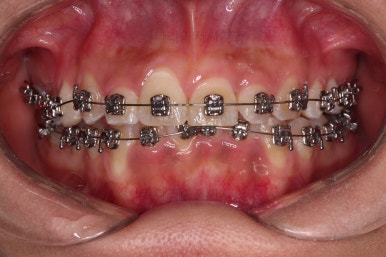

악궁확장 이후에 교정장치를 부착하고 치열을 가지런하게 해줘요.

이번에 사용한 장치는 엠파워 메탈이라고 하는 자가결찰 메탈 장치입니다.

거듭 말씀드렸지만 메탈이라고 다 옛날의 구식 장치가 아니에요.

"자가결찰" 인지 아닌지 여분가 훨씬 중요한데요.

"자가결찰" 메탈장치라면 치료효과가 좋은 "자가결찰"장치의 한 종류이므로 기능이 매우 좋은 장치랍니다.

장치 부착 이후의 느낌도 봐주시고요.

치열이 점점 가지런해지죠?